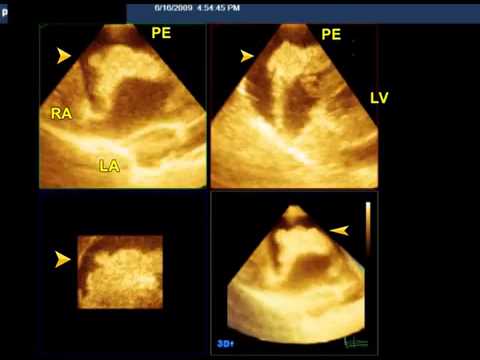

Video 8.3

Video 8.3 (Figure 8.5A) Video shows the relationship of RAA to ascending aorta (AA) and pulmonary artery (PA). The bubble study shows contrast entering the RAA following an intravenous injection. The large echo-free space around the RAA represents pericardial effusion. PE = pericardial effusion. Source: Reproduced with permission from Patel V, et al.